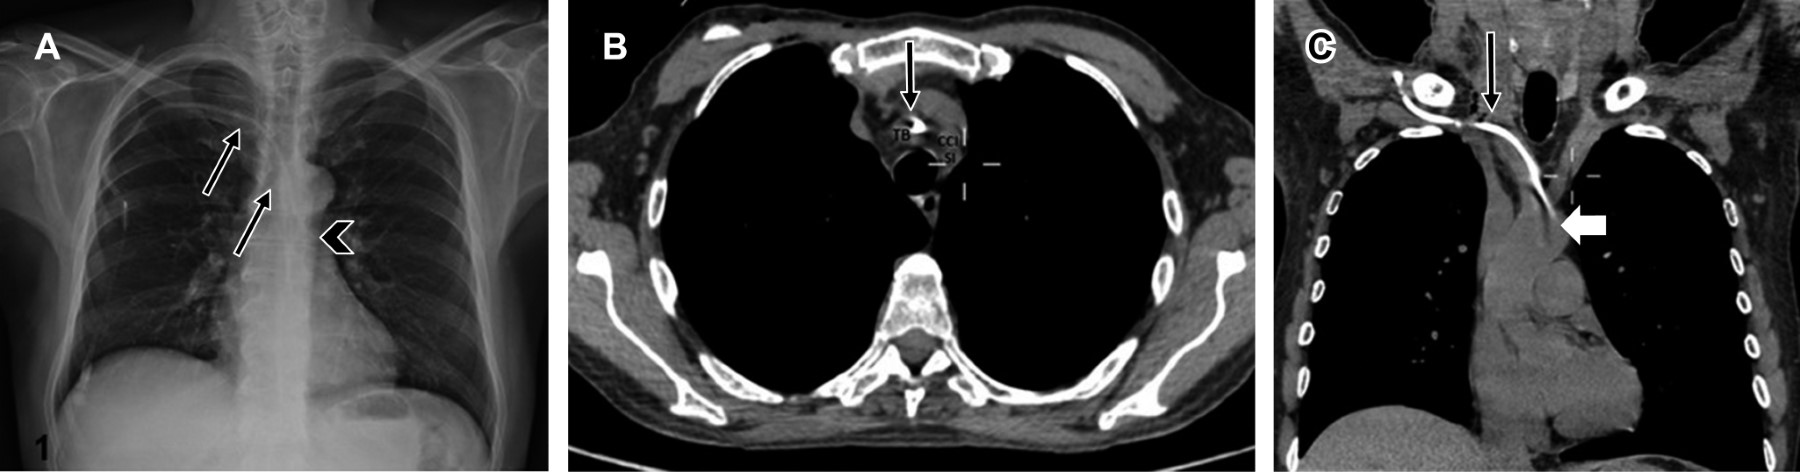

Evaluación radiológica: la evaluación del cateterismo como exitoso, ya sea de acceso yugular o subclavio, debe basarse en el conocimiento de los marcadores anatómicos en la radiografía.3 La identificación inicial del catéter es crucial, y deben tomarse en cuenta los siguientes puntos; el extremo distal del catéter debe localizarse distal a la última válvula venosa que corresponde a la confluencia de ambas venas braquiocefálicas formando la vena cava superior (VCS), que en la placa de tórax se proyecta en el borde interno de la primera costilla y lateral al borde esternal derecho (es valioso comprender que la VCS presenta una estrecha relación con los vasos supraaórticos a este nivel, ya que se localiza anterior a éstos).7,9,18

El trayecto de VCS nos ofrece otras referencias anatómicas, ya que sigue un curso perpendicular y ulterior al segundo y tercer espacio intercostal (línea paratraqueal derecha), alcanzando la unión cavoatrial (Figura 3) antes de ingresar al pericardio (borde superior del tercer cartílago costal derecho), y posteriormente ingresar al saco pericárdico.9 En la radiografía, Baskin KM y colaboradores proponen situar la unión cavoatrial dos cuerpos vertebrales por debajo de la carina. Diversos autores recomiendan que todas las puntas de catéter deben situarse por encima de la carina.9,20

• 2. Extravascular. La ubicación atípica del catéter se sospecha en la radiografía de tórax cuando la línea densa que representa éste se localiza hacia la izquierda de la tráquea o de la columna vertebral;22 la confirmación de este marcador se puede realizar con una tomografía computarizada (Figura 4).1